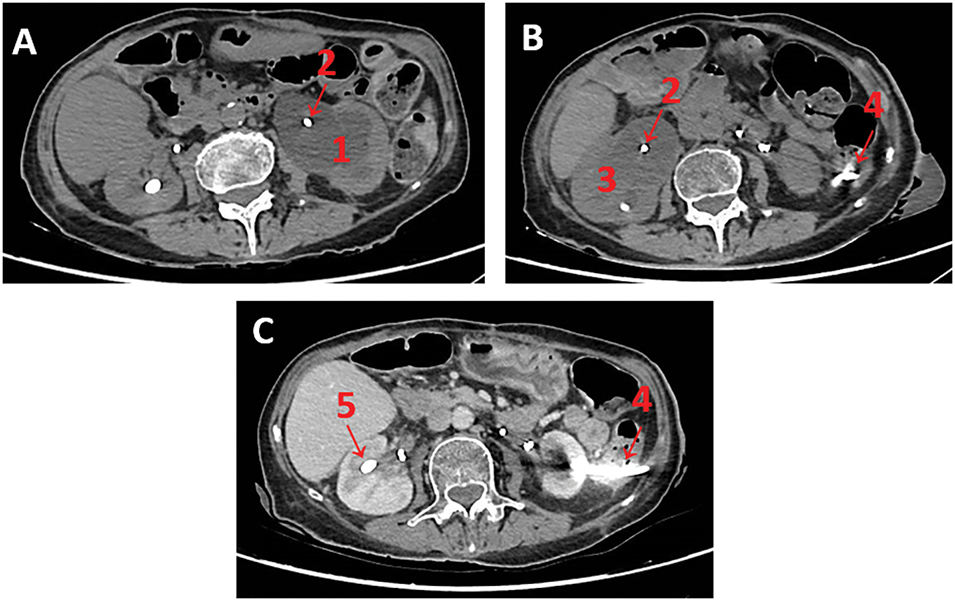

FIGURE 1. Sequential abdominopelvic computed tomography (CT) images. (A) Non-contrast scan showing significant (1) left hydronephrosis and (2) occluded left double J stent; (B) Non-contrast scan raising suspicion for transcolic passage of the (4) left nephrostomy tube; (C) Contrast-enhanced still showing suspicion for transcolic passage of the (4) left nephrostomy tube. Note: (1) left hydronephrosis, (2) occluded double J stent, (3) right hydronephrosis, (4) suspected intracolic trajectory of left nephrostomy, (5) right nephrostomy tube.

Three weeks later, her renal function again started to deteriorate despite an adequately draining nephrostomy with simultaneous oliguria via the bladder. This prompted a non-contrast abdomino-pelvic CT-scan, which revealed interim development of contralateral right-sided hydronephrosis despite appropriate ureteric stent placement. Also reported was an unexpected finding of a possible trans-colic passage of the previously placed left nephrostomy (please see Figure 1B).

An abdominopelvic CT scan was repeated with intravenous contrast. The diagnosis is not straightforward due to artefacts caused by the nephrostomy tube. In fact, our radiologists are unable to give a definitive diagnosis of whether a nephrostomy tube is trans-colic, sub-serosal, or in the pericolic fat (please see Figure 1C).